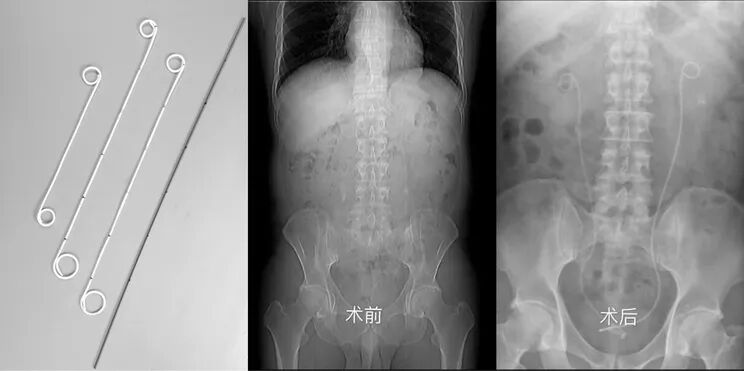

双J管就是输尿管支架管,是一根细长的软管,因其两端卷曲形似英语字"J"而取名双J管。同时,其形状与猪尾巴非常相似,故也叫猪尾巴导管。双J管因厂家不同,材料不同外观上稍有差异,但大体上都是管子中空,其管上有多个侧孔,作用引流尿液、支撑输尿管。

先来看看它的庐山真面目: